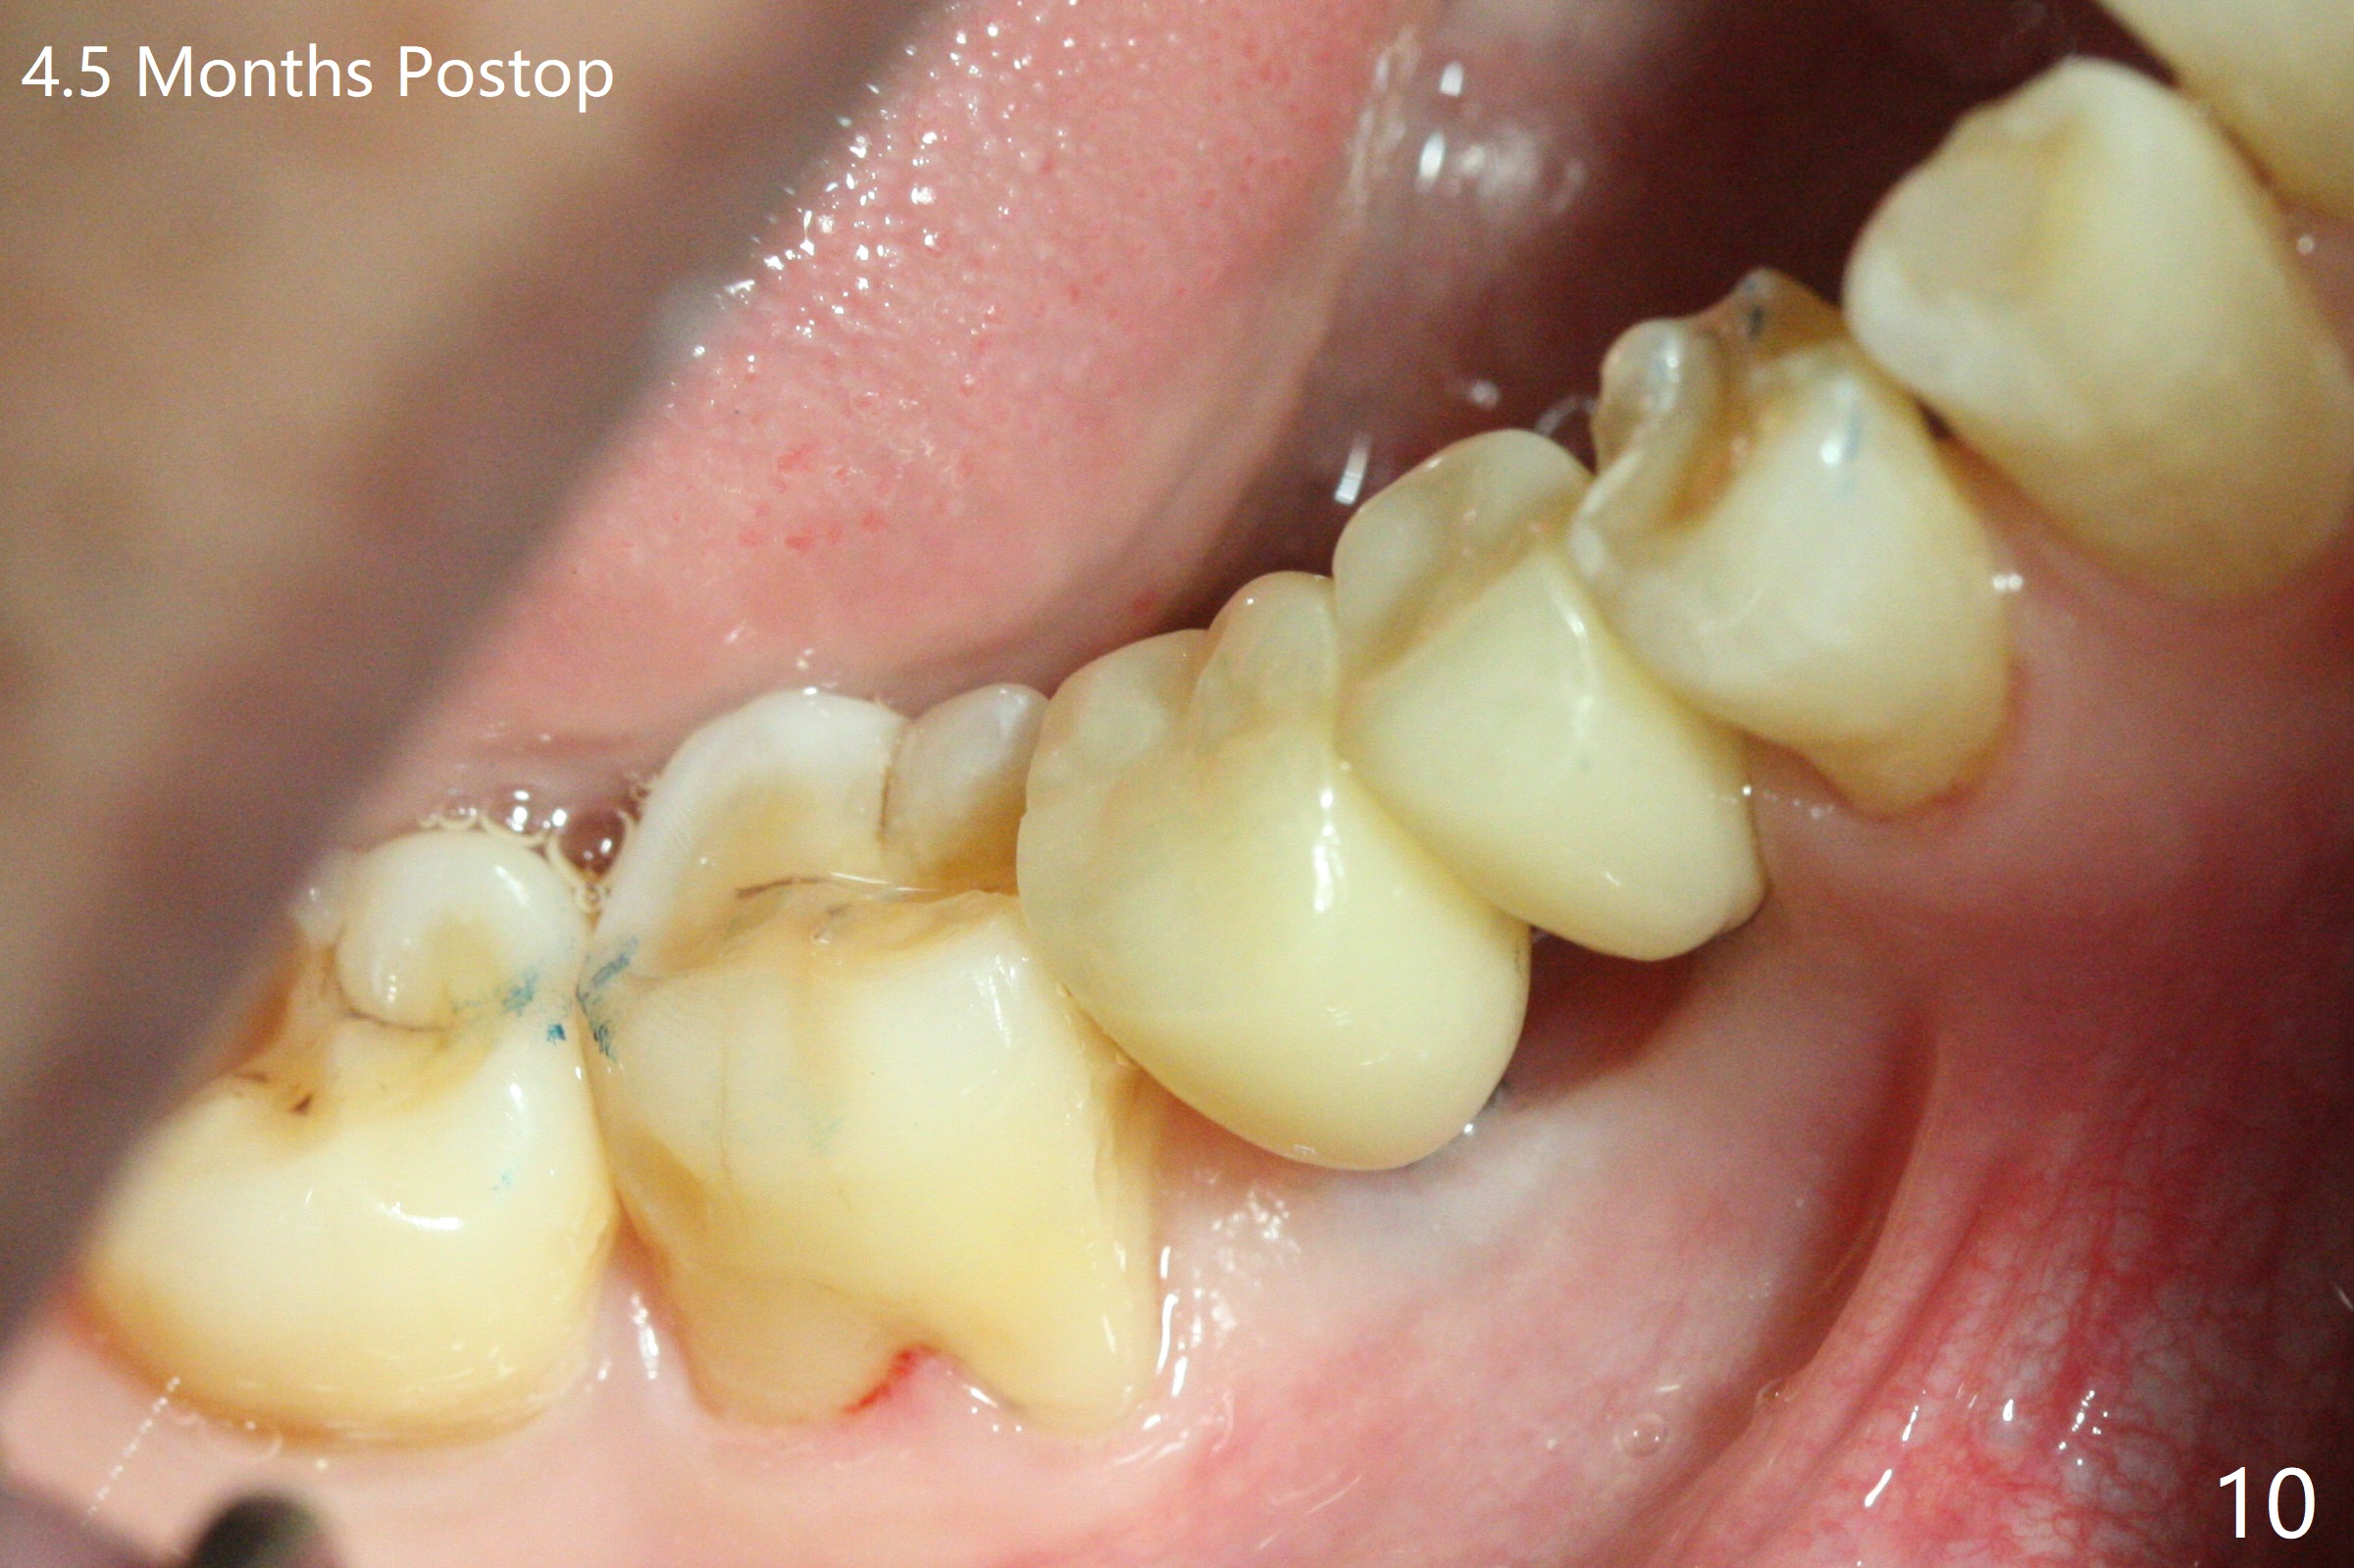

After initial osteotomy using 2.2 mm drill for 10 and 11.5 mm at #29 and 30, respectively, the guide is removed for re-insertion of drills and PA (Fig.1). The osteotomy at #29 is found lingually and in the nonkeratinized gingiva with mild laceration (wish incision to be made before osteotomy); the osteotomy is established a little lingual at #29 (Fig.2) and more or less in the middle of the narrow ridge and #30 (Fig.3). Lindamann bur is used to move #29 osteotomy buccally. A 1.5 mm drill is used to increase the depth free hand before placement of 2.5x10(4) mm 1-piece implants (Fig.4). After adjustment of the implant depth (Fig.5), CT is retaken, which shows proper implant placement (Fig.6,7). Probably due to good oral hygiene, the gingiva around the implants appears to be keratinized 4 months postop (Fig.8). After abutment preparation for margin and parallelism, impression is taken (Fig.9). When the permanent crowns are temporarily cemented, the large gingival embrasure is noted (Fig.10,11). The latter could be reduced by modifying the provisional in the healing stage. In fact the crown at #29 dislodges 2 days post cementation because lingual (Fig.12) and distal (Fig.13) placement. A surgical stent should have been fabricated from RPD for free hand placement!